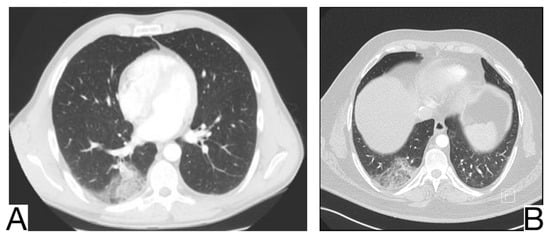

Imaging diagnosis is necessary (Figure 11A,B): ground glass opacities and condensation predominantly in the middle as well as in the lower lobes []; condensations usually show very low CT attenuation concerning their fat content; fibrosis in the chronic stage [,].

Figure 11. Lipoid pneumonia (A). Ill-defined airspace opacity next to the left hilum (B). Atelectasis of middle lobe and ground-glass opacity. Note. Case courtesy of Dr. Aneta Kecler-Pietrzyk, Radiopaedia.org, rID: 62113 (A) and Dr. Abraão Kupske, Radiopaedia.org, rID: 55752 (B).